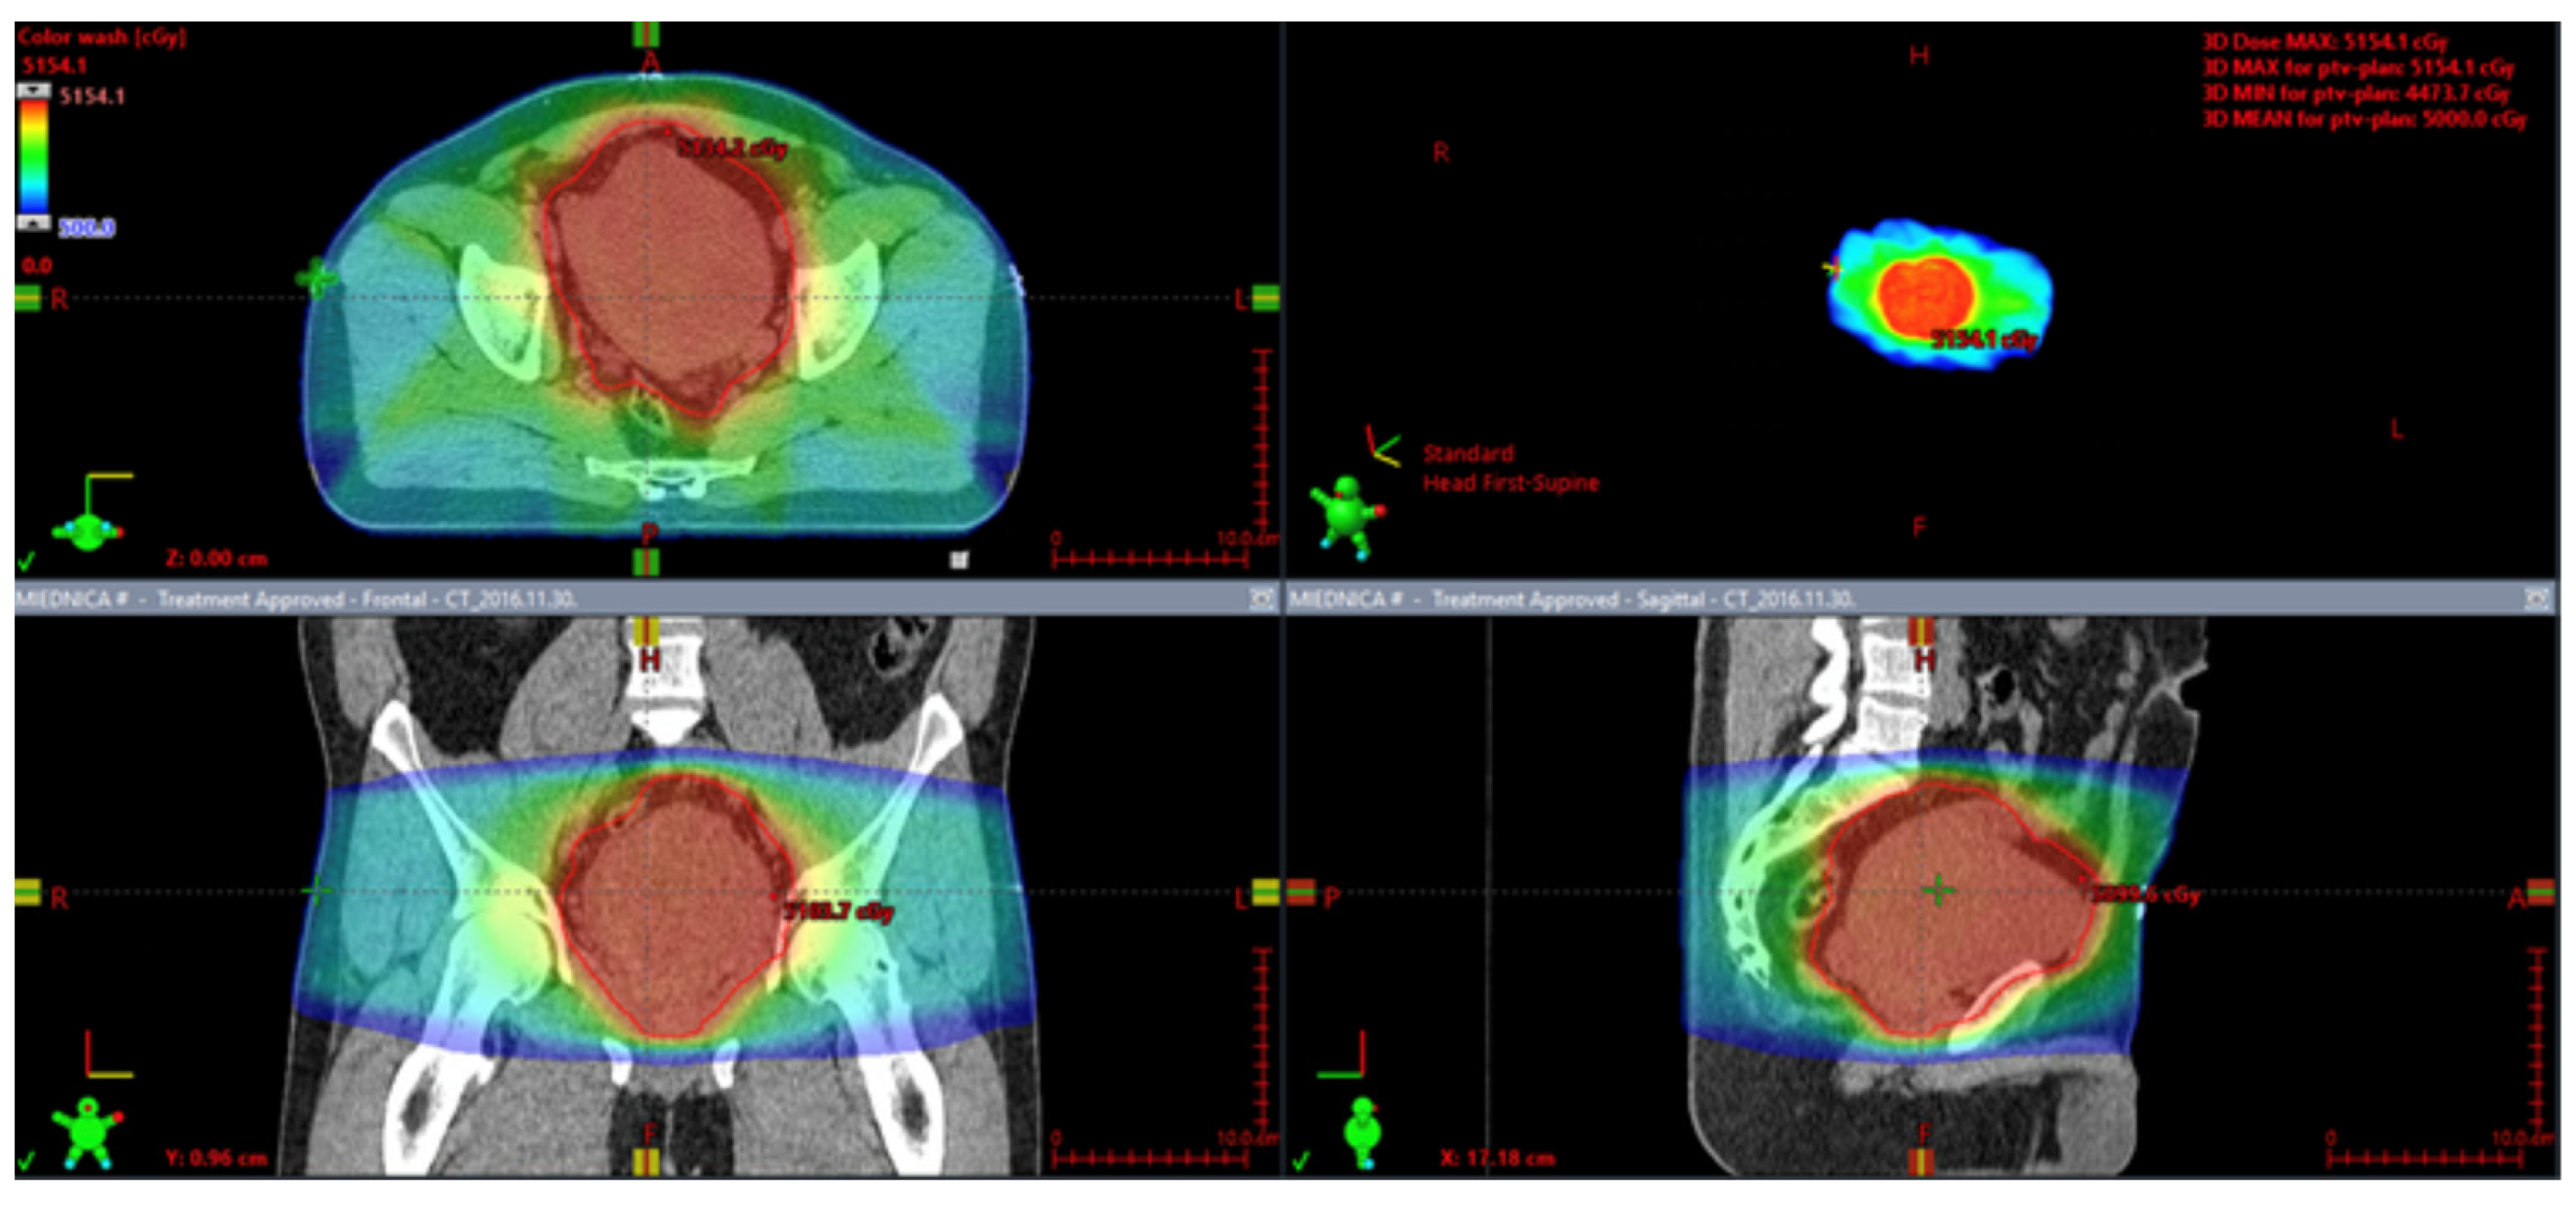

7.2. Perioperative Radiotherapy

7.4. Definitive Radiotherapy